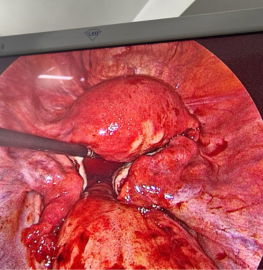

Special Case

27yr female with acute pain abdomen for 2days. Admitted. Pregnancy test positive USG showed mild to moderate fluid in abdomen. Haemoglobin was decreasing. Decided to do diagnostic laparoscopy. After entering into the a dome there was approx 1 lit blood inside. Continuous bleeding from right ovarian cyst. Cauterisation and biopsy done.